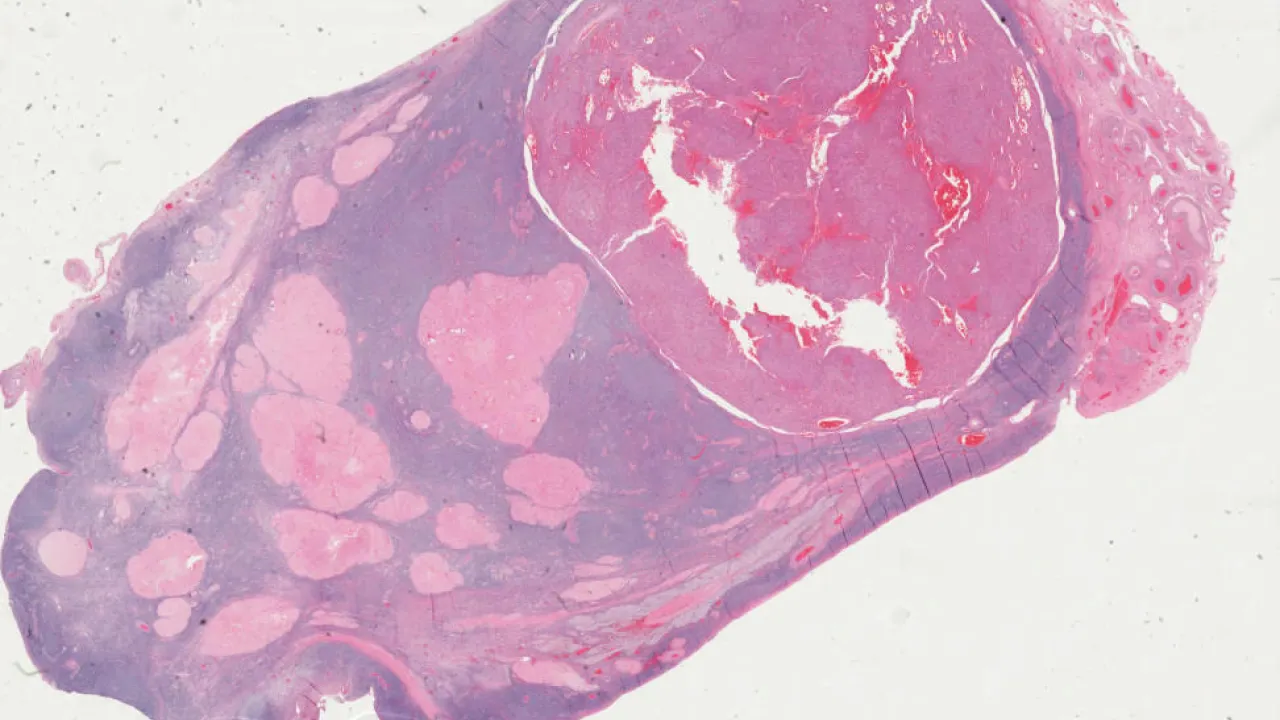

Breast, Benign phyllodes tumour